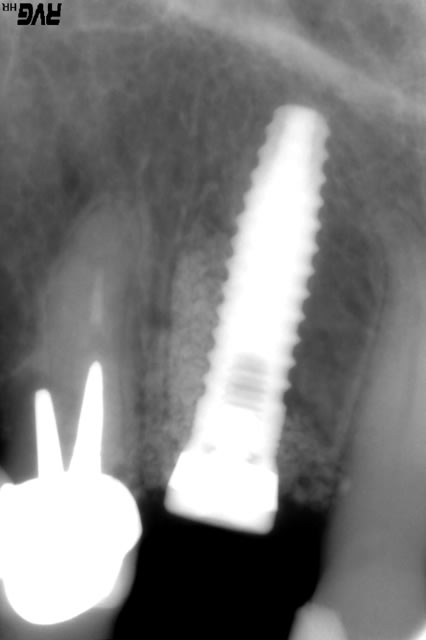

le graftec de TBR, je regarde sa porosité et je mettrai la radio avec

graftek : porosité de 60 à 80 %, ø des pores de 150 à 400 µm, 0,75 cc par seringue, je mets le prix demain

la dernière radio est à 6 mois post op, il y a eu une petite inflammation distale qui m'a fait perdre un peu de hauteur, provoquée par un grain de TCP qui est resté bloqué en surface pendant les vacances cet été; le PBI est revenu à 0 depuis